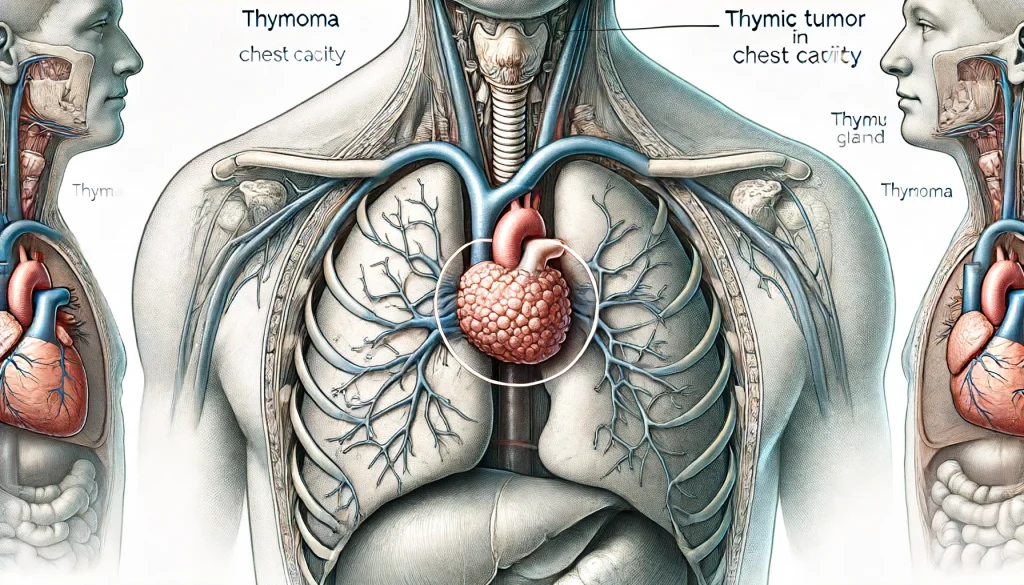

日本全国送料無料商品人気ランキング 胸腺腫(きょうせんしゅ 神戸きしだ - 呼吸器疾患 – Thymoma) 健康・医学の詳細情報

胸腺腫(きょうせんしゅ Thymoma) – 呼吸器疾患 - 神戸きしだ。Nerves of the Thorax: Atlas of Normal and Pathologic。胸腺腫(きょうせんしゅ Thymoma) – 呼吸器疾患 - 神戸きしだ。2024年度 新潟県魚沼産BLコシヒカリ10kg。Thoraco-abdominal CT scan. A shadow (90 mm in diameter) can。数ページ鉛筆による書き込みあり